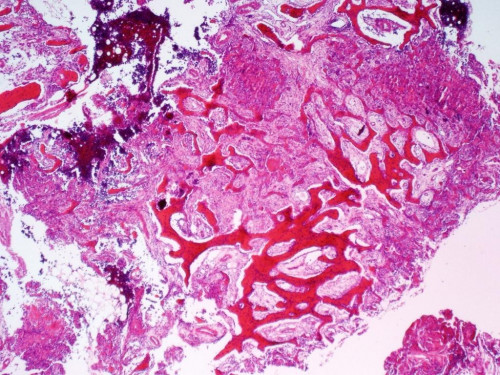

11-jähriges Mädchen. Sie klagt schon seit längerem über Schmerzen im linken Fuß, die insbesondere nachts auftreten. Ihre Mutter tut es anfangs noch als Wachstumsschub ab. Als ihre Beschwerden nach ein paar Wochen aber immer noch nicht verschwunden sondern sogar eher stärker geworden sind, wird die Mutter misstrauisch. Sie bringt ihre Tochter zum Kinderarzt, der eine Bildgebung veranlasst.